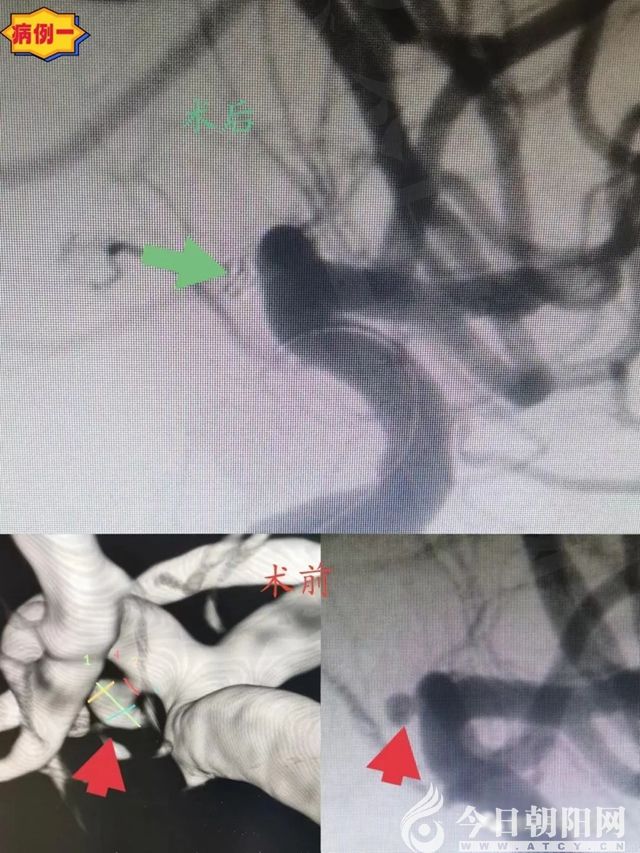

病例一:45歲,女性,以“突發(fā)頭痛伴惡心嘔吐2小時(shí)”為主訴入院。平時(shí)健康,無(wú)基礎(chǔ)病史。查體:GCS評(píng)分15分,頸抵抗,無(wú)其他神經(jīng)系統(tǒng)陽(yáng)性體征。

頭顱CT:彌漫性蛛網(wǎng)膜下腔出血,以環(huán)池及鞍上池為主。DSA:左側(cè)大腦前動(dòng)脈A1段微小動(dòng)脈瘤,瘤體指向下方,大小約2.08mm×1.6mm。診斷:左側(cè)大腦前動(dòng)脈A1段動(dòng)脈瘤,自發(fā)性蛛網(wǎng)膜下腔出血。